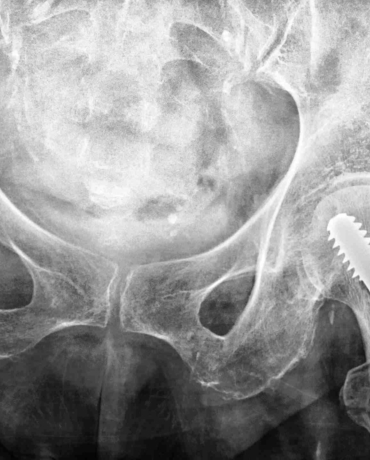

Falls are the leading cause of injury-related hospitalisation in people aged 65 and over. Our research is focused on improving fall-related hip fracture treatment.

Our research has shown that across New South Wales, there is significant variation in the time older people have to wait for their hip fracture surgery, with the conclusion that more could be done to expedite care.

Our other research in the same area has demonstrated that a particular approach to caring for hip fracture patients is associated with a lower 30-day mortality rate. When orthopaedic surgeons and geriatricians look after a hip fracture patient together, the outcomes seem to be better for older people. This approach to care is being recommended across Australia.